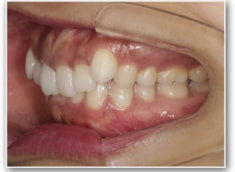

叢生+左下1番先天欠如ケース

治療法:裏側の矯正(リンガルブラケット:舌側矯正)

治療開始1年後